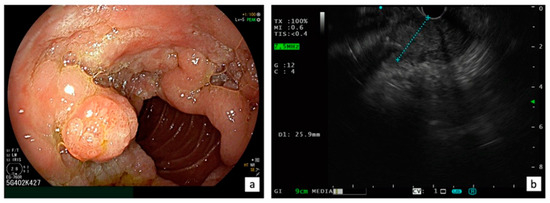

Endoscopic evaluation of ANLs may be challenging using a forward-viewing endoscope. The European Society of Gastrointestinal Endoscopy (ESGE) considers the visualization of the papilla as a research priority for a complete high-quality endoscopy [16]. Thus, cap-assisted upper endoscopy should be indicated when the major papilla is not seen by a gastroscope, but a side-viewing duodenoscopy is recommended for the optimal visualization of the papilla and the assessment of the feasibility of endoscopic resection in presence of ANLs [17] (Figure 1).

Figure 1.

Endoscopic (a) and EUS (b) evaluation of ANLs.

Endoscopic ultrasound (EUS) plays a crucial role in the ANL evaluation, providing an accurate assessment of the size, location, and characteristics of the lesions, including the staging of the depth of tumor invasion into the surrounding tissues such as duodenal wall, biliary duct, pancreatic duct, and pancreatic parenchyma, and the involvement of local lymph nodes, according to the latest TNM classification (Figure 1).